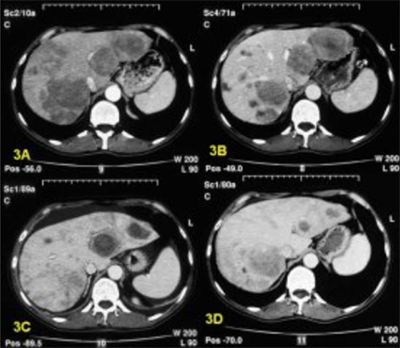

В России ежегодно фиксируется около 450 тысяч новых случаев метастазирования в печень. Основными признаками метастатических поражений печени являются множественные опухолевые узлы (узловые формы), которые вовлекают значительные объемы печеночной паренхимы, с возможной локализацией как в центре, так и на поверхности печени. В 75% случаев наблюдается тотальное поражение печени, в 16% — единичные метастазы, а в 9% — солитарные метастазы. Размер метастазов может варьироваться от небольших (несколько миллиметров) до крупных (несколько сантиметров), они имеют округлую или неправильную форму и четкие контуры.

Проводятся диагностические исследования для определения местоположения первичной опухоли, а также применяются инструментальные методы для визуализации метастазов и оценки степени поражения печени. К таким методам относятся УЗИ, МРТ/ПЭТ с контрастным веществом, ПЭТ-КТ и ангиография. Если выявить первичную опухоль не удается, для установления гистологического диагноза выполняется биопсия измененных участков печени.